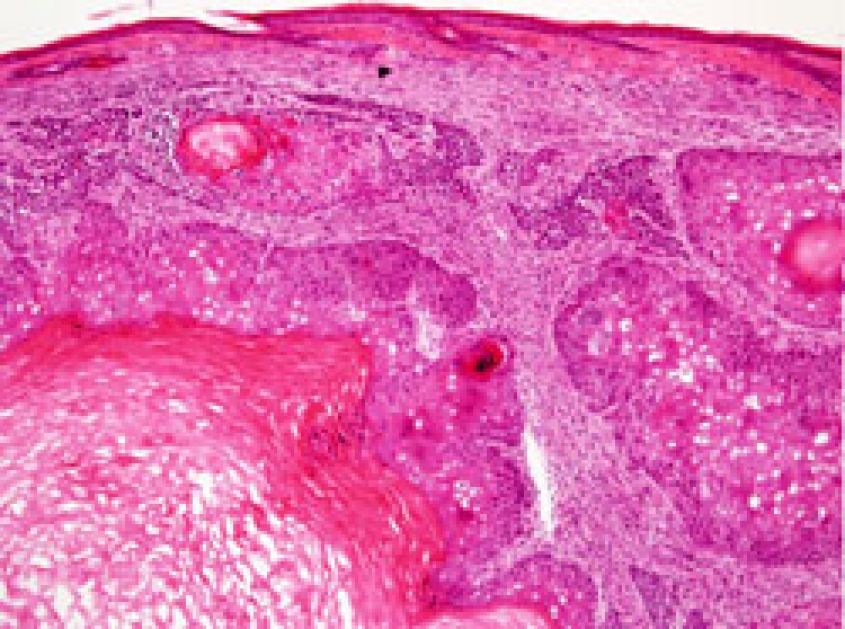

Our previous work identified hair follicle stem cells as particularly susceptible to tumorigenic transformation. In the context of Ras/p53 mediated skin cancer formation, hair follicle stem cells can act as cancer cells of origin, whereas their descendant progeny, the transit amplifying cell population, is completely resistant to transformation. Moreover, we determined that during the resting phase of hair follicle, stem cell quiescence can act as a natural block to tumor initiation. This process of tumor suppression via stem cell quiescence may apply to other organ systems, and in cases where stem cells cycle very rarely, this could account for cancer emergence in later stages of life.